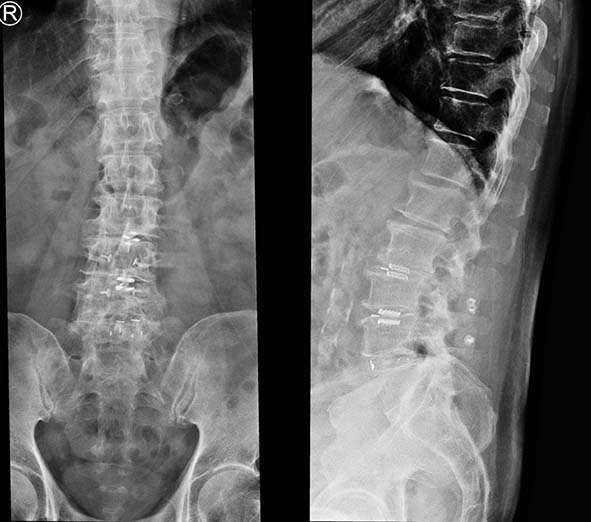

高市72歲郭姓老翁(圖三左二)4年間兩度接受腰椎融合術,下背部僵硬痠痛及坐骨神經痛仍未改善,影響步行且夜不成眠長期憂鬱,經親友轉介七賢脊椎外科醫院,微創脊椎外科副院長朱晟瑋(圖三左一)建議移除腰椎固定金屬融合器,再施做顯微手術神經減壓,搭配無鋼釘支架穩定加大神經椎間孔,術後隔天能下床走動,一週後疼痛明顯改善,接續與身心科醫師商討減量用藥,恢復如常生活。

朱晟瑋表示,腰椎無鋼釘穩定器微創術先移除阻礙腰椎活動鋼釘及脊突間金屬融合器,接續施作顯微神經減壓術,搭配骨塊與支架穩定器術加固腰椎及擴大神經椎間孔空間,消除坐骨神經壓力。